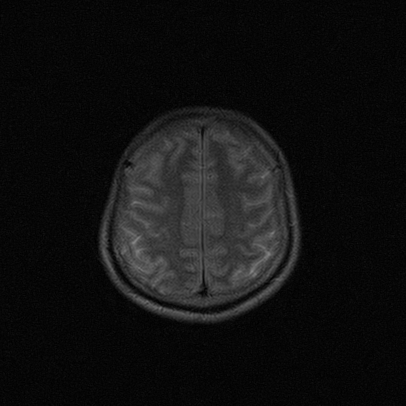

标题: MRI2064:少见病例。男性52,视力下降多年。 [打印本页]

标题: MRI2064:少见病例。男性52,视力下降多年。

考虑第四脑室室管膜瘤并梗阻性脑积水;部分性空蝶鞍;左侧上颌窦粘膜下囊肿。